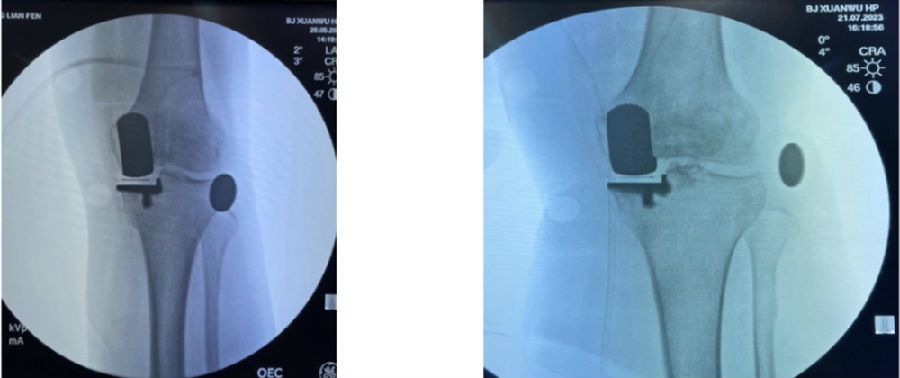

12、术后拍片

目前,笔者团队已经做了70多例,在早期探索过程中可能会出现一些问题,但是之后基本上都是比较好的,术后片子比较赏心悦目。

典型病例

简单总结一下近期的数据,共20例患者的20例膝关节,男5人(25%),女15人(75%),左膝11例(55%),右膝9例(45%)。平均年龄69.8+5.6岁。以±3°作为整个导板设计规划与实际实施的幅度标准。术前规划与术后实际型号没有任何区别,是100%的符合度。

胫骨后倾角有95%的符合度,胫骨内翻角是100%的符合度;胫骨旋转仍然存在一个相对大的差距,但是比传统工具要更好,有70%的病人胫骨内旋角是在范围之内。

股骨在冠状面的角度上也是比较好的表现,股骨内翻角存在95%的符合度,股骨内外旋转角稍差一点,但也达到70%。目前唯一还存在不太满意的地方就是矢状面上股骨假体低头,这个角度偏差度和术前规划差距较大,有50%的准确。